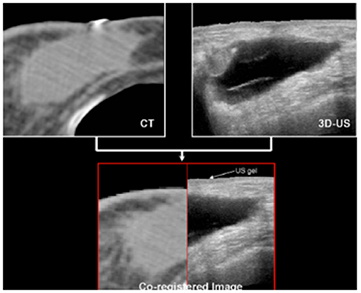

A similar 3DUS study (Berrang et al 2009) for accelerated partial breast irradiation (APBI) with photon beams used the Restitu system (now Clarity: Elekta, Stockholm, Sweden). They also registered 3DUS and CT images and didn't use FM. Figure 5 from this work compares the seroma cavity as seen on CT and US images. They obtained a 3DUS-CT co-registration that was accurate to within 2 mm or less in 19/20 patients. They reported that CT seroma visibility was reduced with dense breast parenchyma, smaller seroma volume, and smaller volume of excised breast tissue, while US seroma clarity was not affected by these factors. They also noted that US imaging had improved interobserver consistency compared with CT in 8/20 cases.

Figure 5. CT image of breast seroma cavity with the cavity indicated in light grey (top left) and US image of the non-echogenic cavity visible in dark grey (top right). Bottom: co-registered image (the mismatch at the skin is attributed to the US gel layer on top of the breast). Adapted from Berrang et al (2009), with kind permission.